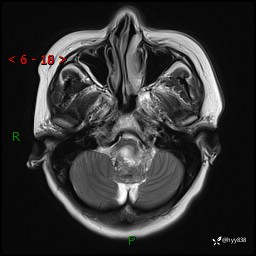

性别:女

年龄:47岁

简要病史:头晕1年余,间断恶心不伴呕吐

颅脑MRI平扫+DWI